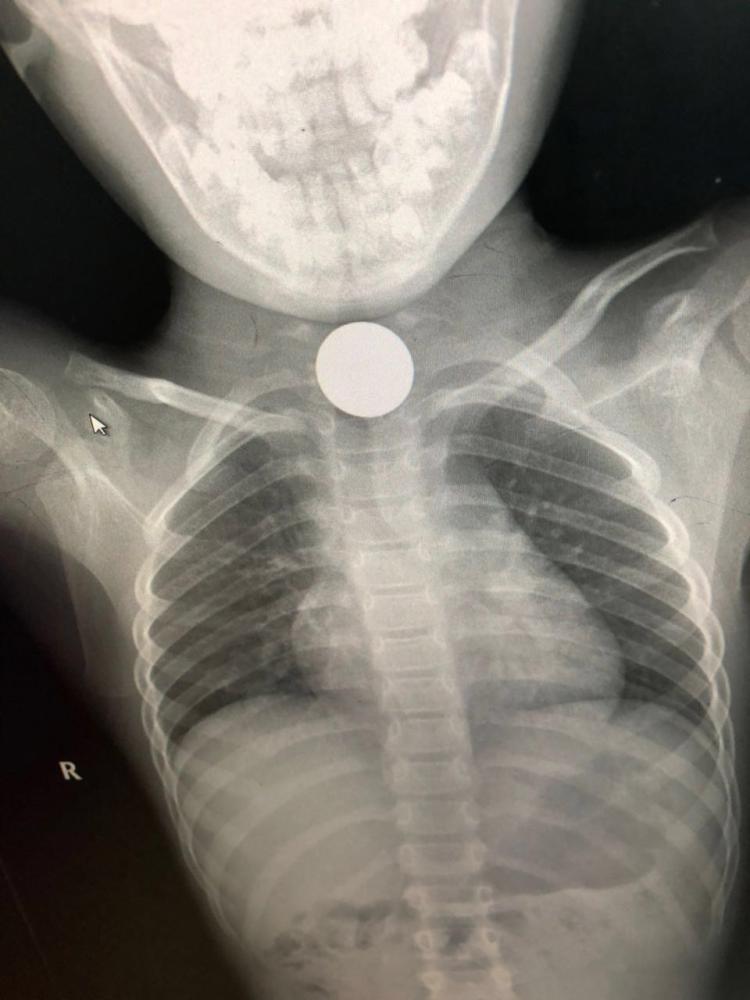

تمكن فريق طبي متخصص في مستشفى القريات العام من استخراج جسم معدني في الثلث الأعلى من المريء لطفلة تبلغ من العمر 5 سنوات مما أضطر الأطباء لإجراء التحاليل والأشعة اللازمة.

وكشفت الأشعة وجود جسم غريب، مما استدعى اتخاذ قرار بالتدخل الجراحي، وأوضحت صحة القريات أن المريضة تتمتع بصحة جيدة وحالتها مستقرة.